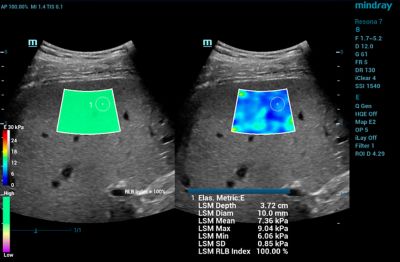

• Shearwave Elastography